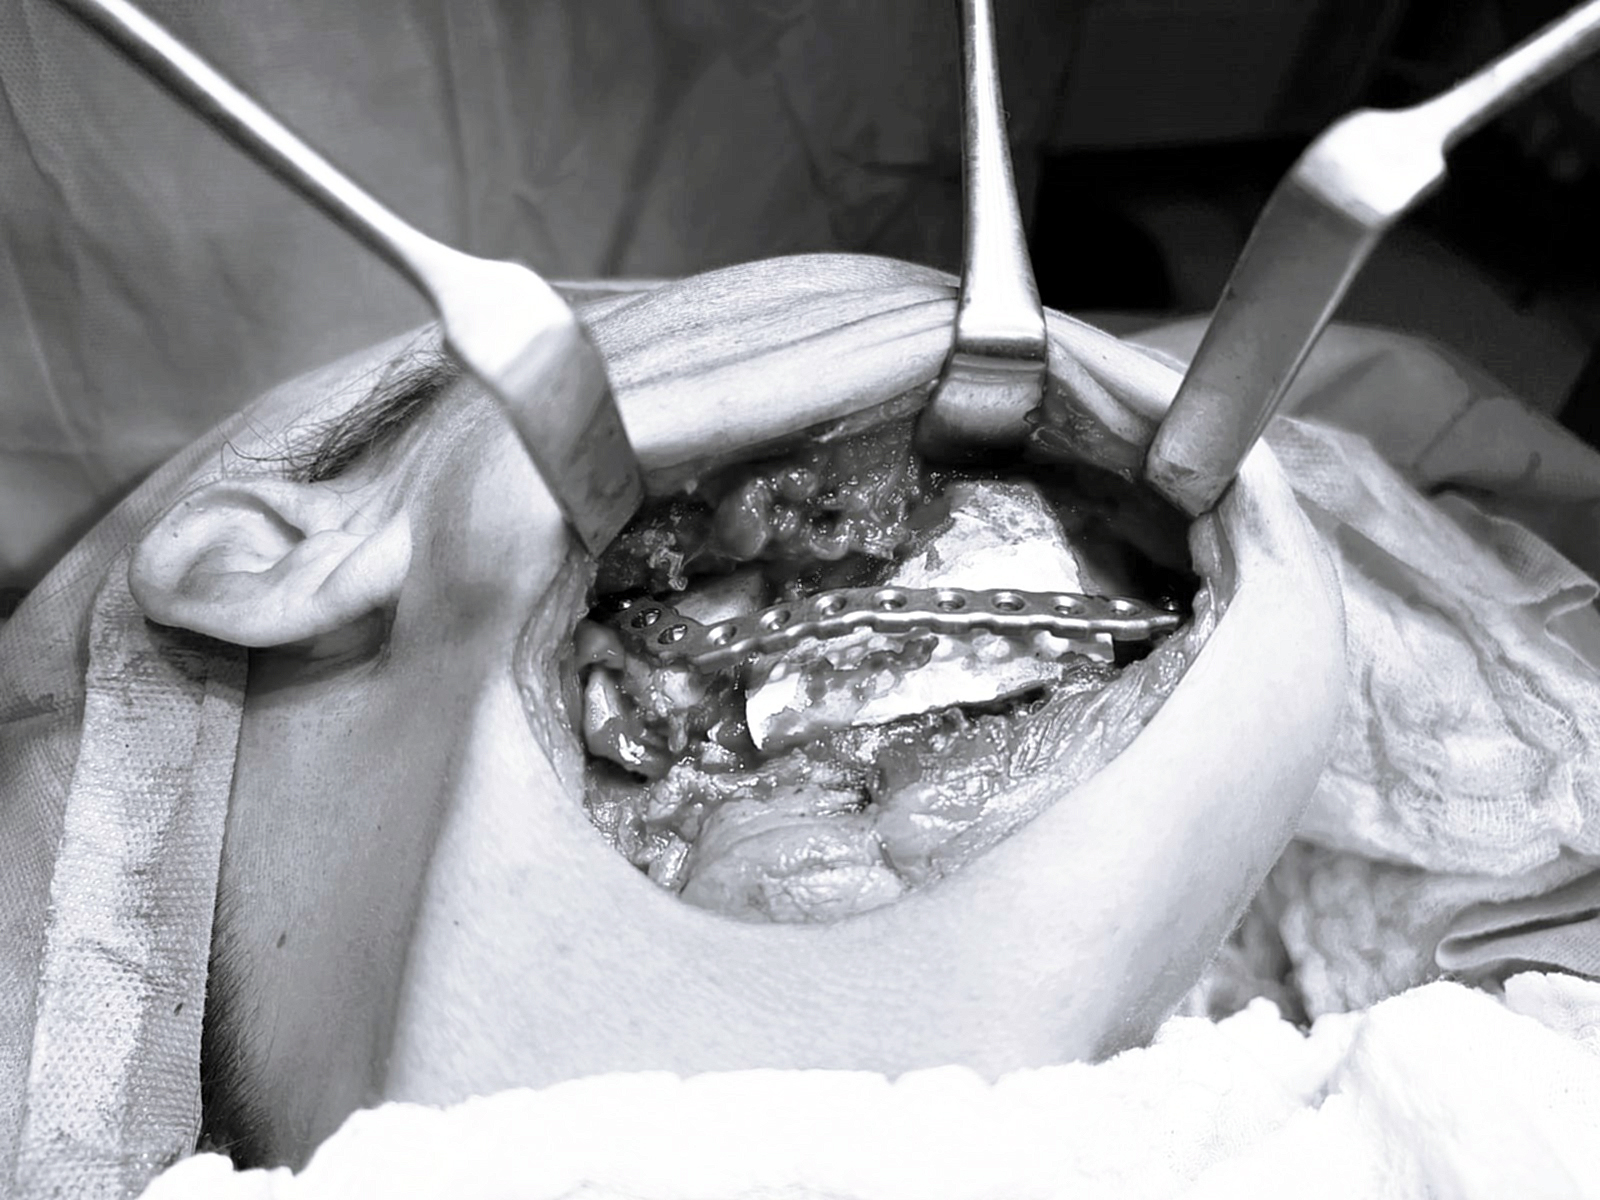

Para una correcta planificación, el equipo médico realizó estudios de imágenes en tres dimensiones, lo que permitió analizar en detalle la zona afectada y preparar previamente una placa de titanio adaptada a la anatomía del paciente, posibilitando una reconstrucción inmediata durante la cirugía.

La intervención consistió en la extracción completa del segmento de la mandíbula comprometido por el tumor, a través de un abordaje por debajo de la mandíbula, una vía segura que permite trabajar directamente sobre la zona afectada sin riesgos innecesarios.

“La planificación previa con estudios en 3D nos permitió anticiparnos a la cirugía, adaptar la placa de titanio antes de ingresar al quirófano y lograr un procedimiento más preciso, seguro y con mejores resultados para el paciente”.